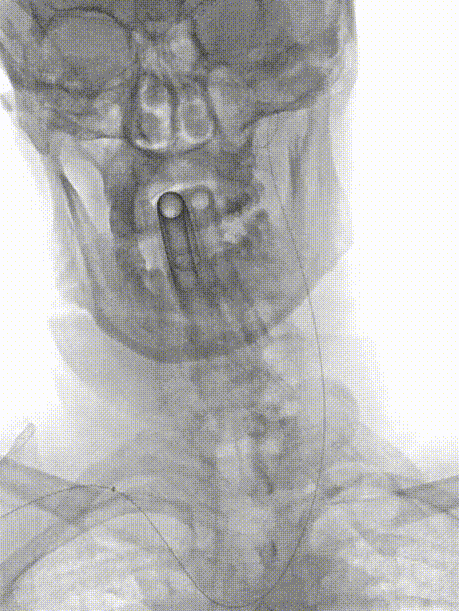

右侧桡动脉穿刺建立入路,交换技术直接经260cm泥鳅导丝置入6F 115cm 中间导管。

术中3D证实明确左侧大脑中动脉重度狭窄,完成测量并选取治疗角度。